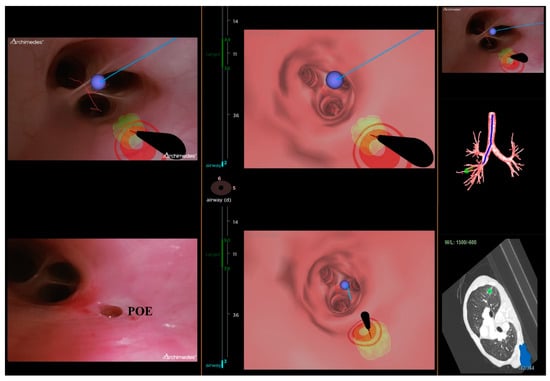

On the day of the ENB procedure, all patients underwent the inspiratory and expiratory 1 mm CT images with the placement of a navigational tracking pad (vPad2 Patient Tracker, INS-0050, Veran Medical, St Louis, MO, USA) on the anterior chest to create a virtual airway map (Veran Medical, St Louis, MO, USA). After the identification of the target lesion, the planning route to the pulmonary lesion was created by the software. Then, all patients were placed in a supine position and under general anesthesia. The peri-operative monitor was according to standard bronchoscopy monitoring protocols. Veran ENB was then used to locate, register, and navigate to the lung targets in accordance with the manufacturer’s instructions [21] (Figure 2). The routine procedure of ENB involved the only use of ENB without additional complementary tools, such as fluoroscopy and radial endobronchial ultrasound. Two chest surgeons performed the ENB procedures (Y. Y. C. and T. W. H., both had more than five years of experience with bronchoscopic procedures and a mean of 100 procedures·physician−1·yr−1). An electromagnetic tip-tracked biopsy instrument (Always-On Tip Tracked Forceps, 1.8 mm OD, Serrated Cup INS-0372, Veran Medical) was inserted via a bronchoscope with an outer diameter of 5.9 mm (Olympus BF-1TQ290) or 5.5 mm (Olympus BF-H190). The performing physician may use a needle aspiration instrument (Always-On Tip Tracked 21ga ANSO Cytology Needle INS-0392, Veran Medical). The biopsy instrument was navigated to the target lesion for the subsequent procedure. There were no other procedural techniques (e.g., additional bronchial washing, bronchoalveolar lavage, or cytology brushing).

Figure 2. Veran electromagnetic navigational bronchoscopy leading to the lesion.